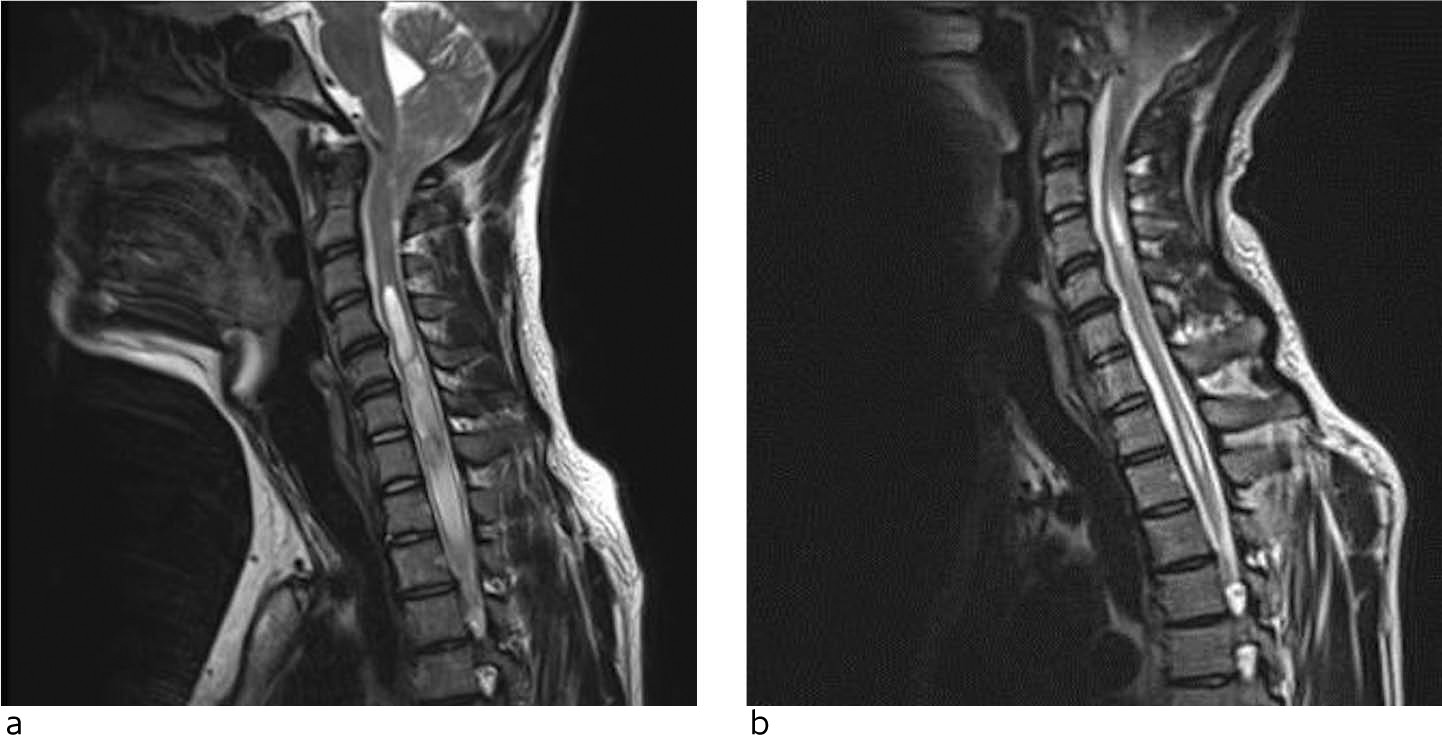

Hos ca. 50 % av pasientene påvises syringomyeli, en cystisk utvidelse av ryggmargens sentralkanal (figur 3). Omfanget kan variere fra et lite segment av ryggmargen til en langstrakt (holocord) syringomyeli. Det finnes forskjellige teorier om hvordan syringomyeli ved Chiari-malformasjon type 1 oppstår. Likevel er ennå ikke alle aspekter av denne problemstillingen godt forklart (12).

MR er den klart foretrukne diagnostiske metoden. Dersom man vil kartlegge alle relevante anatomiske forhold, er det best å utføre MR caput med sekvenser som gir informasjon om flyt av hjernevæske i kraniocervikalovergangen (flytsensitive sekvenser), samt MR totalcolumna for å utelukke syringomyeli og/eller tegn til ryggmargstjoring. Ved vår avdeling ser vi ofte pasienter henvist kun på bakgrunn av lavtliggende lillehjernetonsiller påvist ved MR som bare omfatter hodet eller nakken. Dette er imidlertid ikke tilstrekkelig for vurdering av kirurgisk behandling. CT har liten plass i utredningen og brukes kun ved mistanke om skjelettanomalier i kraniocervikalovergangen eller der MR-undersøkelse er kontraindisert.

Det er viktig å poengtere at syringomyeli, som ved Chiari-malformasjon type 1 er konsekvens av trange forhold i foramen magnum, i de aller fleste tilfeller vil minske eller stabilisere seg spontant etter dekompresjon alene (figur 3). Det er dermed vanligvis ikke nødvendig med direkte inngrep mot syrinx. Åpning eller drenering av syrinx (syringo-subaraknoidal eller -pleural shunt) utføres kun i ytterst sjeldne situasjoner hvor syringomyeli progredierer radiologisk eller klinisk selv etter tilfredsstillende dekompresjon av foramen magnum.